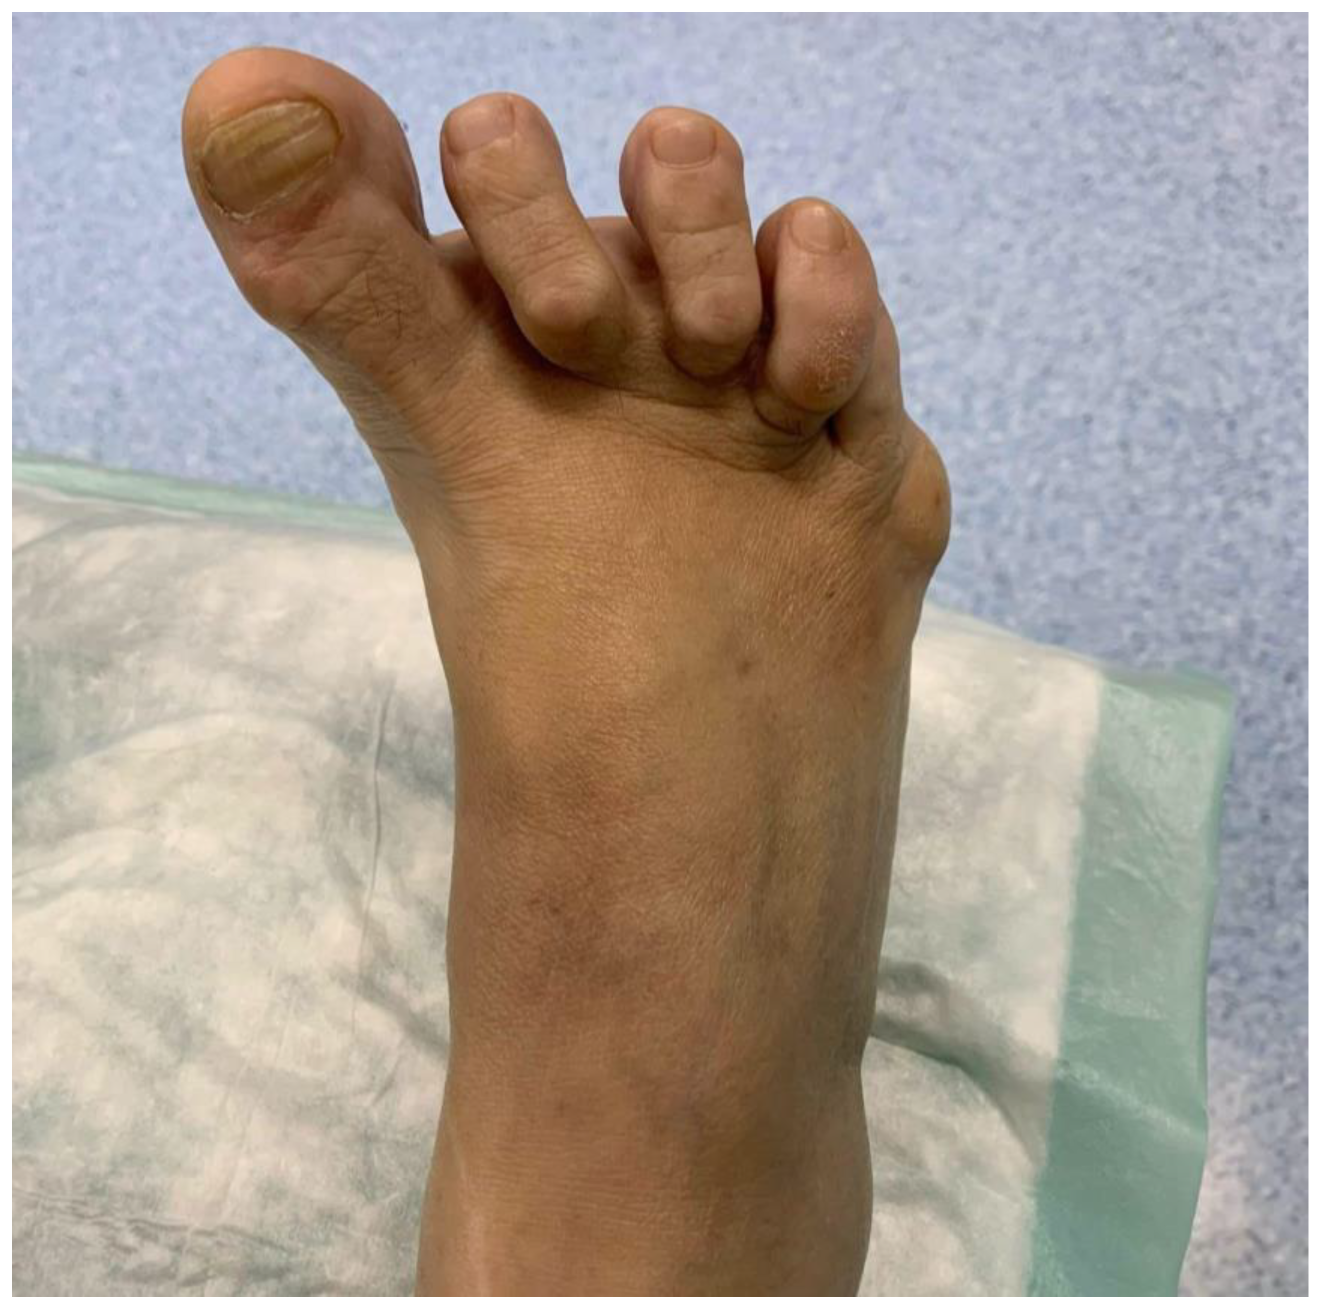

Clinical examination reveals a varus deviation of the first toe and claw position of the lesser toes (Figure 1). Manual reduction of the varus is not possible, and movement of the hallux is painful. In addition, the position of the hallux prevents the patient from putting on shoes normally.

Figure 1.

Image of the appearance of the right foot with preoperative hallux varus.